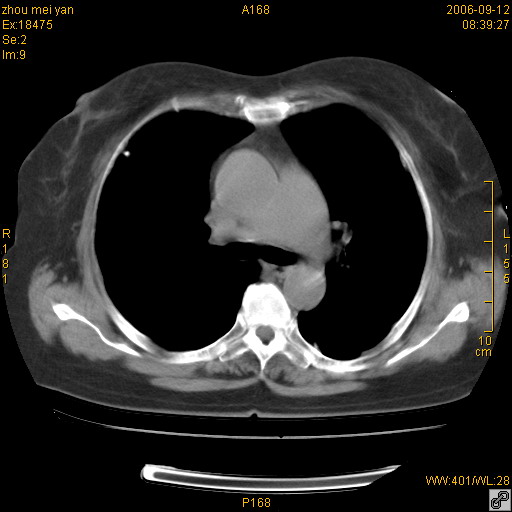

患者、女、55岁。因心率失常住院检查ct发现胸部多发结节。腹部b超肝、胆、胰、脾、肾、子宫附件未见异常。无结核病史,无粉尘接触史。请大家来会诊。谢谢!

病变位于胸膜,多发结节,边界清楚,内见小结节状钙化。其它未见异常。

双侧胸膜多发结节,形态不规则,边缘较清楚,每一个结节中心似乎都有钙化点的特征,与胸膜广基相切。临床无结核病史,无粉尘接触史。

影像表现十分有特点:双侧肋胸膜及膈胸膜广泛散在分布大小在2至6mm左右,较大病灶中心可见钙化。

考虑恶性胸膜间皮瘤可能性大,病灶位于胸膜,以宽基地与胸膜相连,呈结节样改变,部分病灶内可见点状钙化影。请各位老师多多指导!